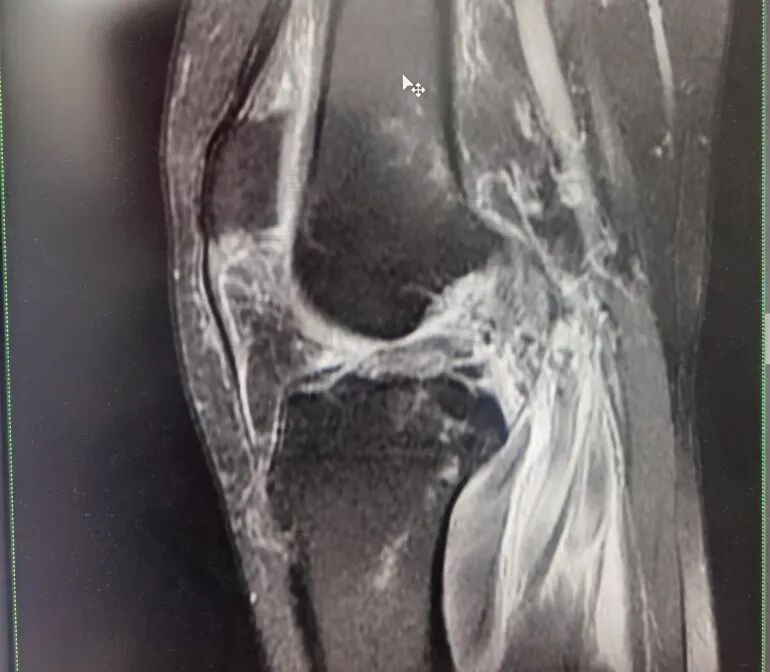

进一步完善检查,发现患者除头部损伤外,左膝严重损伤,其左膝“内侧半月板撕裂,外侧半月板撕裂”,左膝关节“内侧副韧带完全断裂,前十字韧带断裂,外侧副韧带损伤”伴“左侧髌韧带损伤”。

骨科王怀波主任解释,患者受伤后疼痛难忍,因外伤导致膝关节功能严重受限,关节稳定性严重丧失,活动时伴有恐惧感。经运动医学详细查体,结合膝关节MRI提示,患者遭遇了前交叉韧带,内侧副韧带,内外侧半月板联合损伤,属于膝关节严重复合伤。“前交叉韧带又称前十字韧带,作为膝关节里面重要的韧带之一,是膝关节从胫骨前方到股骨的后方的一根斜韧带,可以控制膝关节旋转。损伤的原因主要包括运动损伤和车祸损伤,最常见的损伤是股骨止点的撕裂。当前交叉损伤以后,病人对于加速跑、旋转都会丧失功能。”